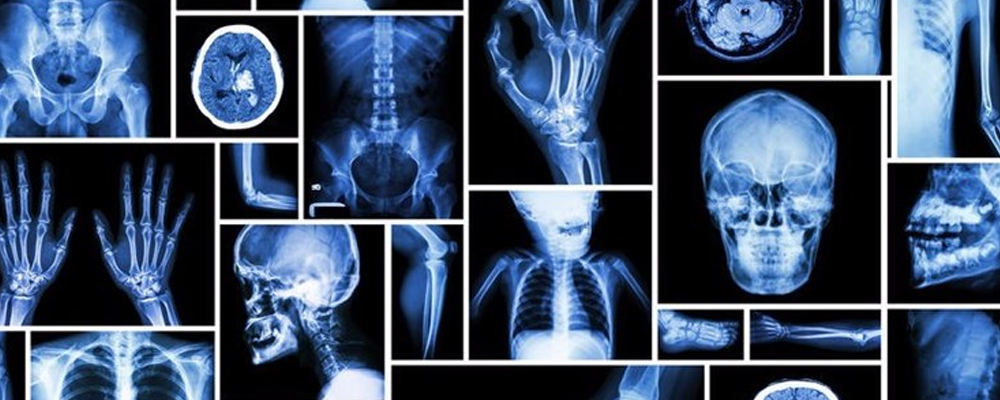

An X-ray is a quick, painless test that produces images of the structures inside your body — particularly your bones.

X-ray beams pass through your body, and they are absorbed in different amounts depending on the density of the material they pass through. Dense materials, such as bone and metal, show up as white on X-rays. The air in your lungs shows up as black. Fat and muscle appear as shades of gray.

X-ray technology is used to examine many parts of the body.